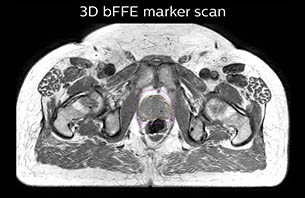

Using the mDIXON and 3D bFFE images, the RT planner marks the position of the nickel-titanium fiducial markers, and contours are transferred to the digitally reconstructed radiographs (DRRs). Reference image matching is based on these markers. “In the rare cases, where visualization of the fiducial markers fails, we do a CT to confirm their location,” Dr. Keyriläinen notes.

MR-only simulation workflow The 3D T1W FFE mDIXON sequence provides in-phase, water and fat images in one acquisition. Target and organs-at-risk are delineated on the 3D T2W TSE images. Prostate GTV is shown in orange, PTV in purple. The 3D bFFE sequence is used by the planner to mark the position of the fiducial markers (gold anchors) and contours are transferred to the digitally reconstructed radiographs (DRRs).

Based on the 3D T1W mDIXON images, MR-based density maps (MRCAT) are automatically generated. The VMAT (Volumetric Modulated Arc Therapy) plan is generated in TPS, based on MRCAT as primary image set. During the commissioning phase, dosimetric agreement between MRCAT-based and CT-based dose plans was studied and differences in the PTV dose were found to be minimal (<1% for most patients). Average difference in PTV mean values was 0.8% over the study group (n=62).